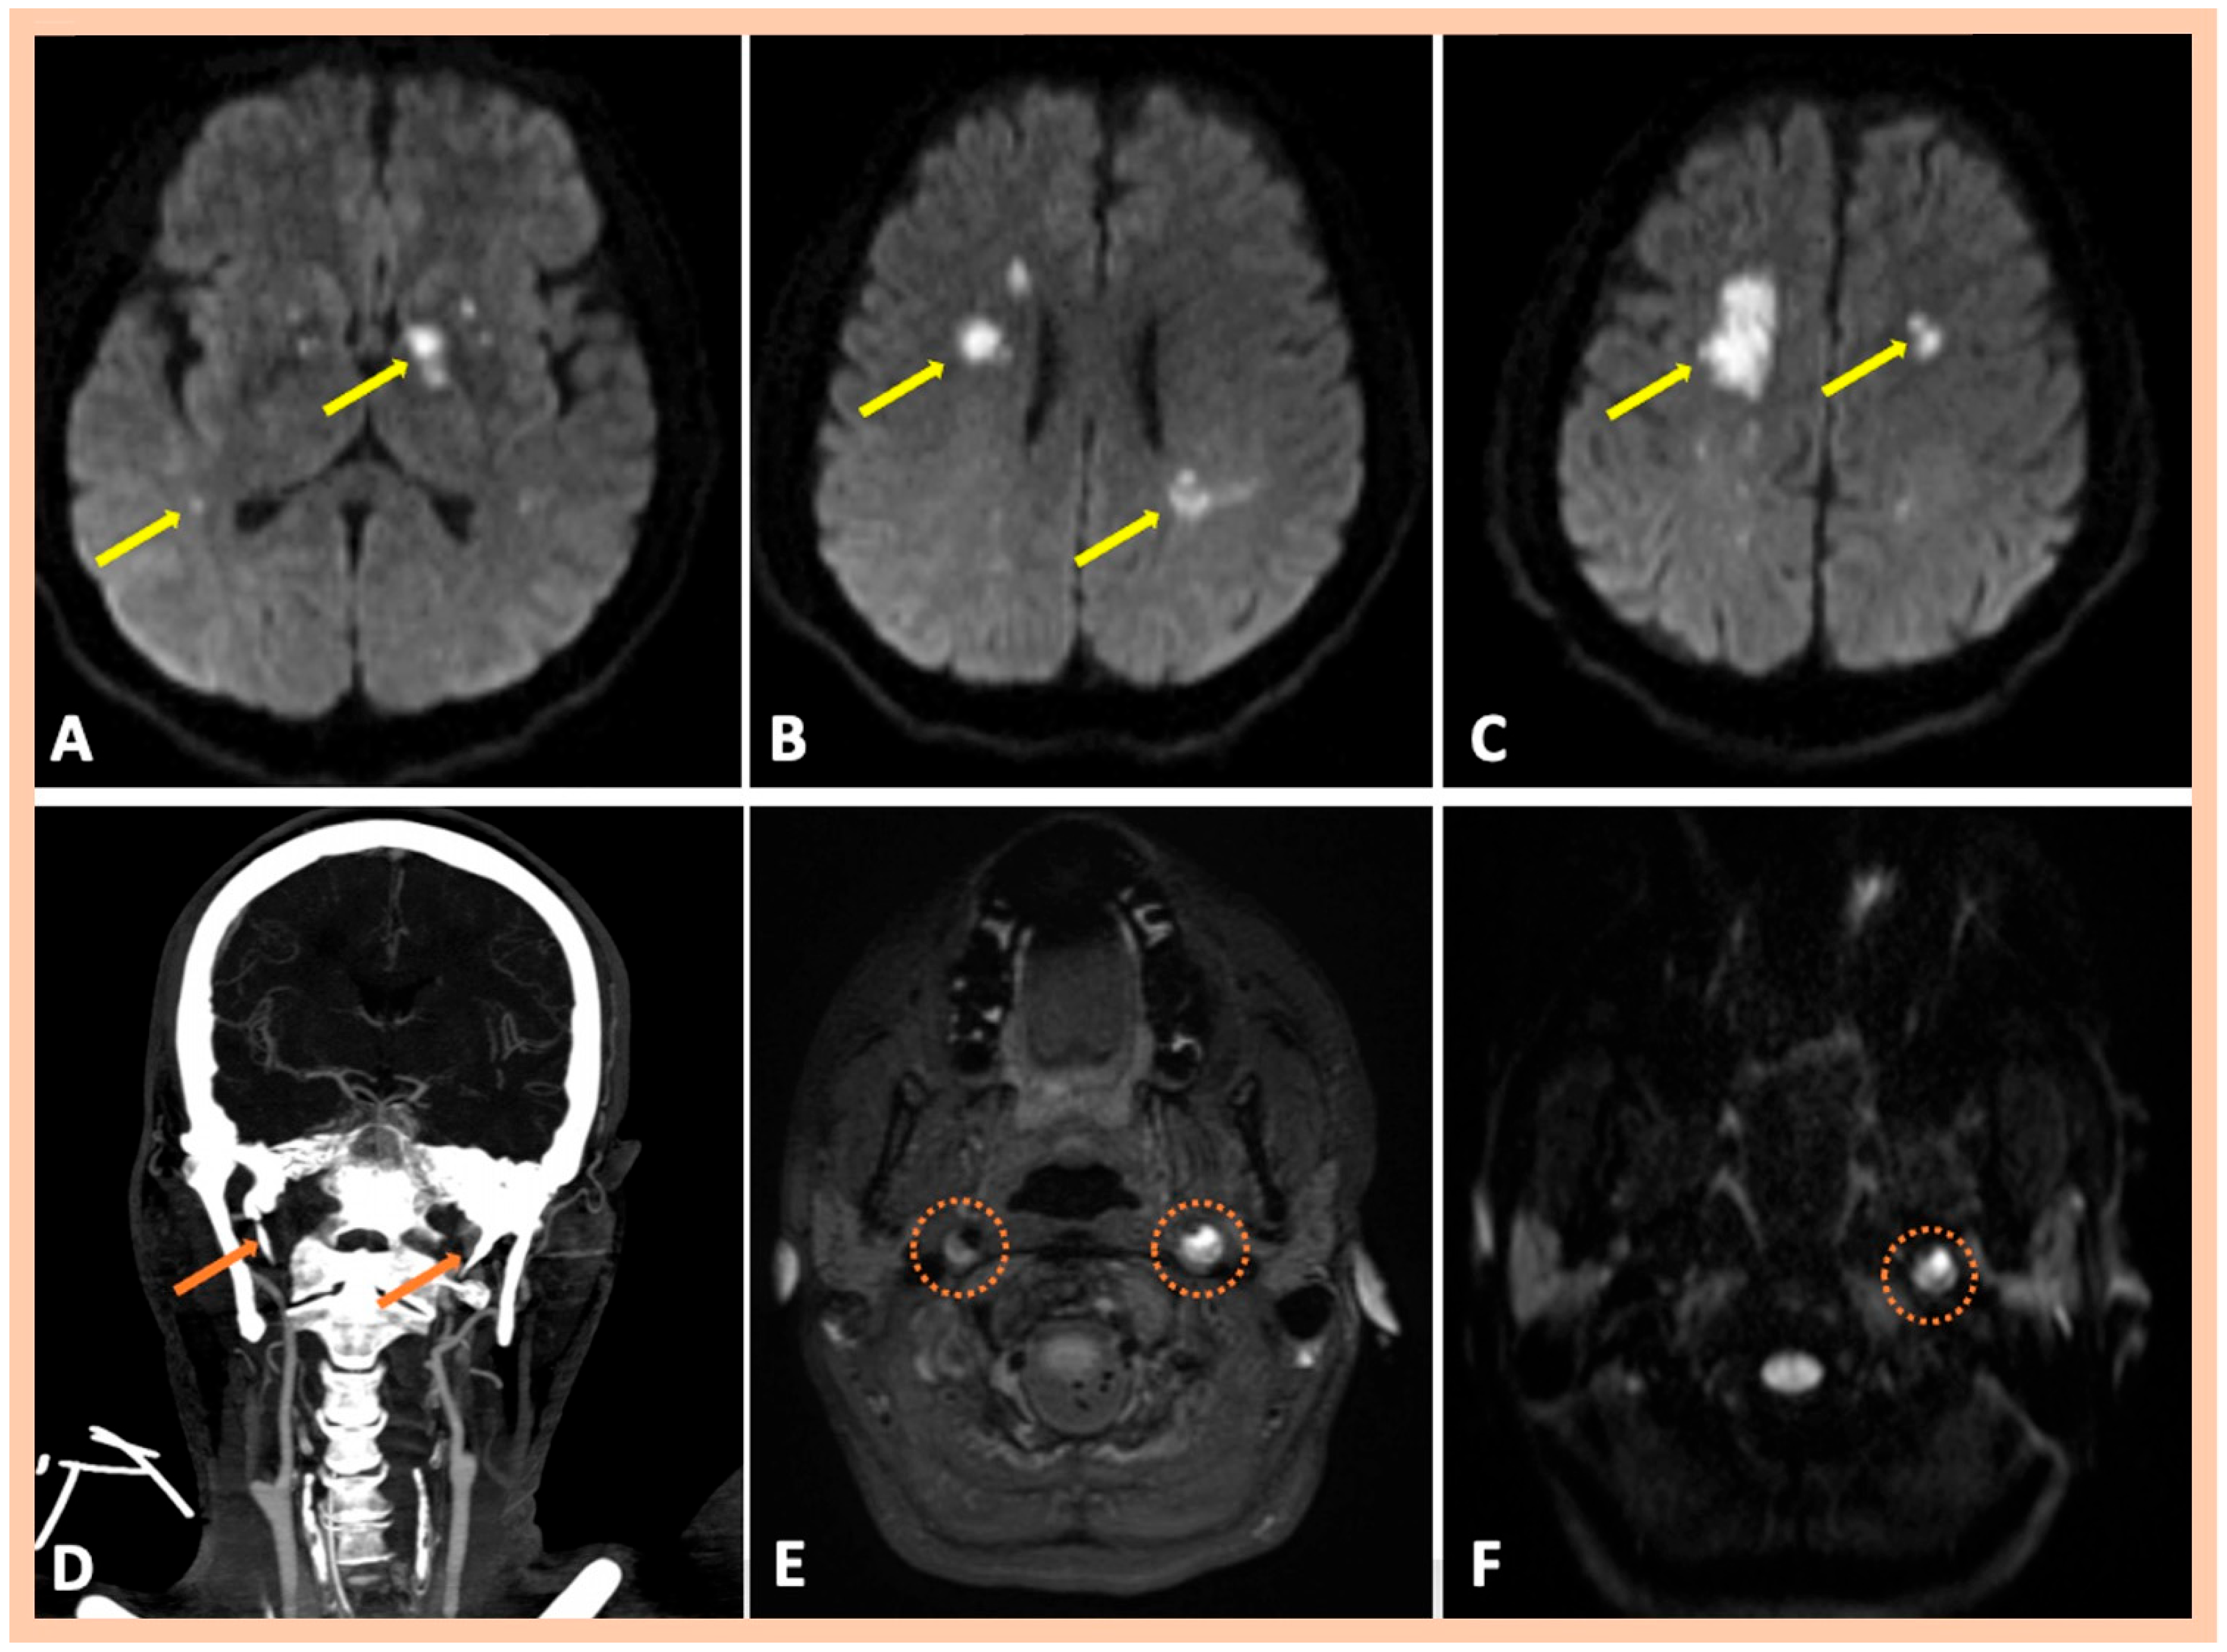

| Pat. #9 | Acute left MCA infarction | Right internal carotid near occlusion along the cervical segment of the artery Left internal carotid “flame-like” occlusion (≈0.5 cm above the bifurcation) | Intramural hematoma along the cervical and proximal petrous artery segments of the right and left ICAs | Confirmed MRA findings | Asymptomatic right and symptomatic left ICA dissections | 2 | No |

| Pat. #11 | Acute multiple left MCA infarctions | Stenosis along the distal cervical and proximal petrous segments of the right ICA with dissecting pseudoaneurysm along the proximal segment of the right ICA dissection Left internal carotid “flame-like” occlusion, above the bifurcation | Intramural hematoma along the cervical segment of the right ICA Intramural hematoma along the cervical and proximal petrous artery segments of the left ICA | Confirmed MRA findings Mild wall abnormalities and segmental dilatations of the lumen were also observed along the V2 vertebral artery segments bilaterally | Asymptomatic right ICA dissection and symptomatic left ICA dissection | 2 | Mild wall abnormalities of the trunk of the right renal artery, without stenosis, indicative of fibromuscular dysplasia |